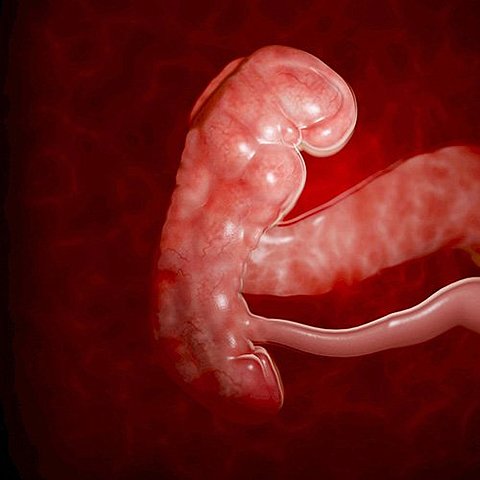

• Quinta semana

Quinta semana

En la quinta semana de embarazo, el embrión mide entre 1 y 2 milímetros. Durante estas primeras y cruciales semanas, sus órganos vitales, huesos y sistema nervioso inician su desarrollo. El embrión se ha dividido en tres capas, que darán lugar a los futuros órganos del bebé: el ectodermo, el endodermo, y el mesodermo.

• Sexta y séptima semana

Sexta y séptima semana

Progresa el desarrollo de la traquea, la laringe y bronquios. La cavidad oral y nasal comienzan a separarse, se forma el paladar. Se encontraron más las piernas y los brazos que parecen aletas. Es la osificación de los miembros inferiores.